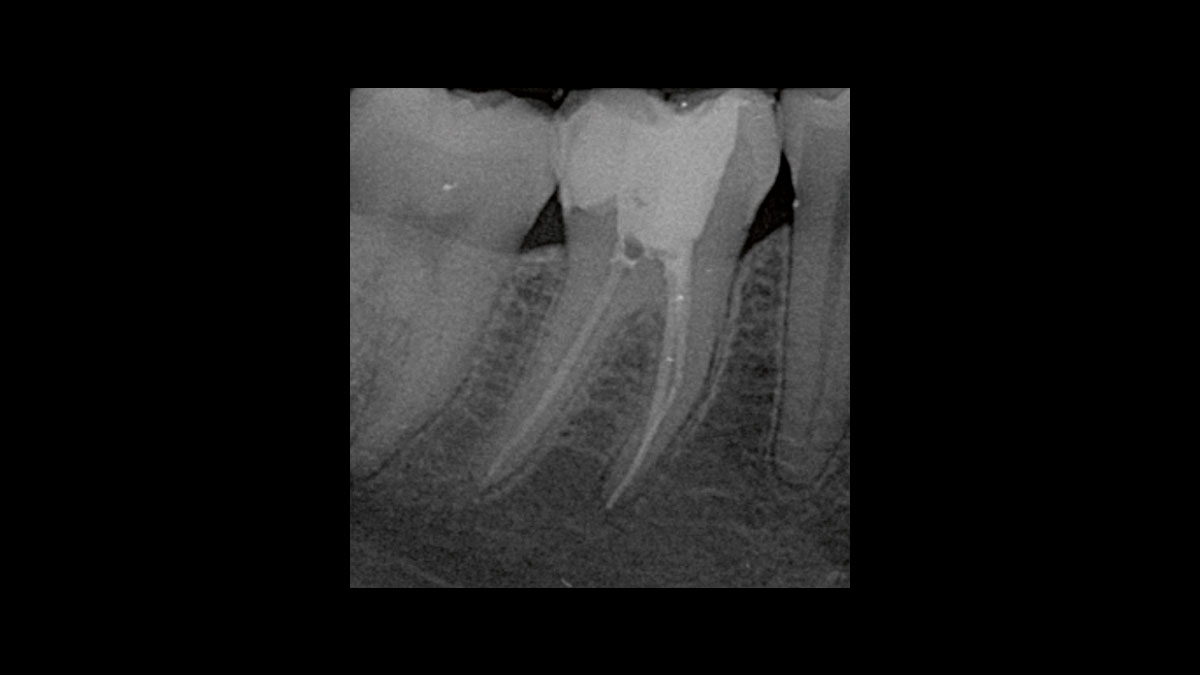

Endodoncia

Las siguientes aplicaciones se presentan en los videos y las imágenes:

• Reducción de bacterias en procedimientos endodónticos

• Reducción de gérmenes de la gangrena

Reducción de bacterias en procedimientos endodónticos